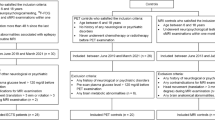

Participants

We conducted this retrospective study, by enrolling patients with TLE, who underwent evaluations for epilepsy surgery from August, 2019 to September, 2020 at Taichung Veterans General Hospital (TCVGH). All methods were performed in accordance with the relevant guidelines and regulations. Their epilepsy histories were obtained, and they at least completed the following comprehensive phase I studies: vEEG, high-resolution brain MRI, PET imaging, and neuropsychological evaluations. In concern of altered thalamic connectivity in focal to bilateral tonic–clonic seizures29, we selected patients who received these exams at the time when no secondarily generalized tonic–clonic seizures occurred for at least 6 months. Patients with brain tumors, severe psychiatric disorders, a history of head trauma or stroke, and temporal-plus epilepsy were excluded. This study was approved by the Institutional Review Board of TCVGH (CE18306B). The informed consent was obtained from all subjects and/or their legal guardian(s).

The18F-FDG PET images were co-registered with the MPRAGE images, and then segmented into the six subfields (Fig. 1). Their volumes and the SUVs were calculated individually. The detail methods were described in the “Supplementary materials”.

We identified 24 patients with left-TLE (L-TLE) and 15 patients with right-TLE (R-TLE). The demographic characteristics of both groups showed no statistically significant differences (Table 1), including age, gender, seizure duration, seizure onset age, educational years, the number of ASMs, and individual IQ scores. The ratio of ever secondary generalization, history of febrile convulsion, the configurations of hippocampal morphologies (sclerosis, normal, or enlargement) were also similar in both groups. We excluded one of the L-TLE patients for calculating the correlation between the asymmetrical indices and the four main IQ scores because he did not complete the comprehensive neuropsychiatric exam.